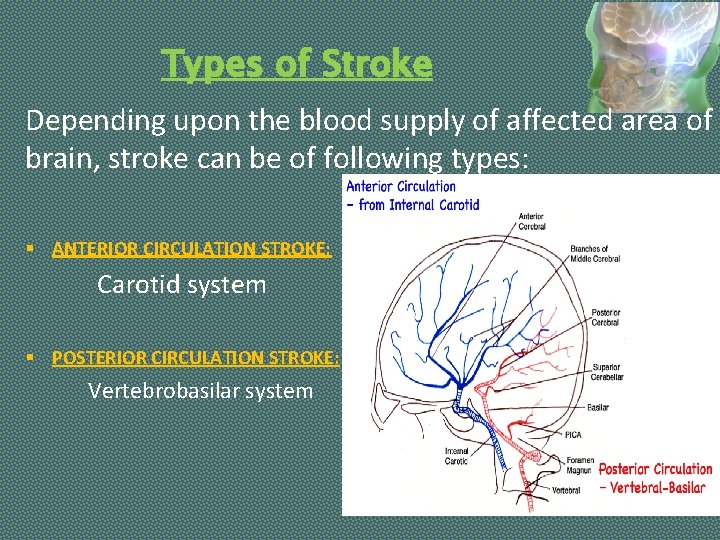

Types of Stroke Depending upon the blood supply of affected area of brain, stroke can be of following types: § ANTERIOR CIRCULATION STROKE: Carotid system § POSTERIOR CIRCULATION STROKE: Vertebrobasilar system